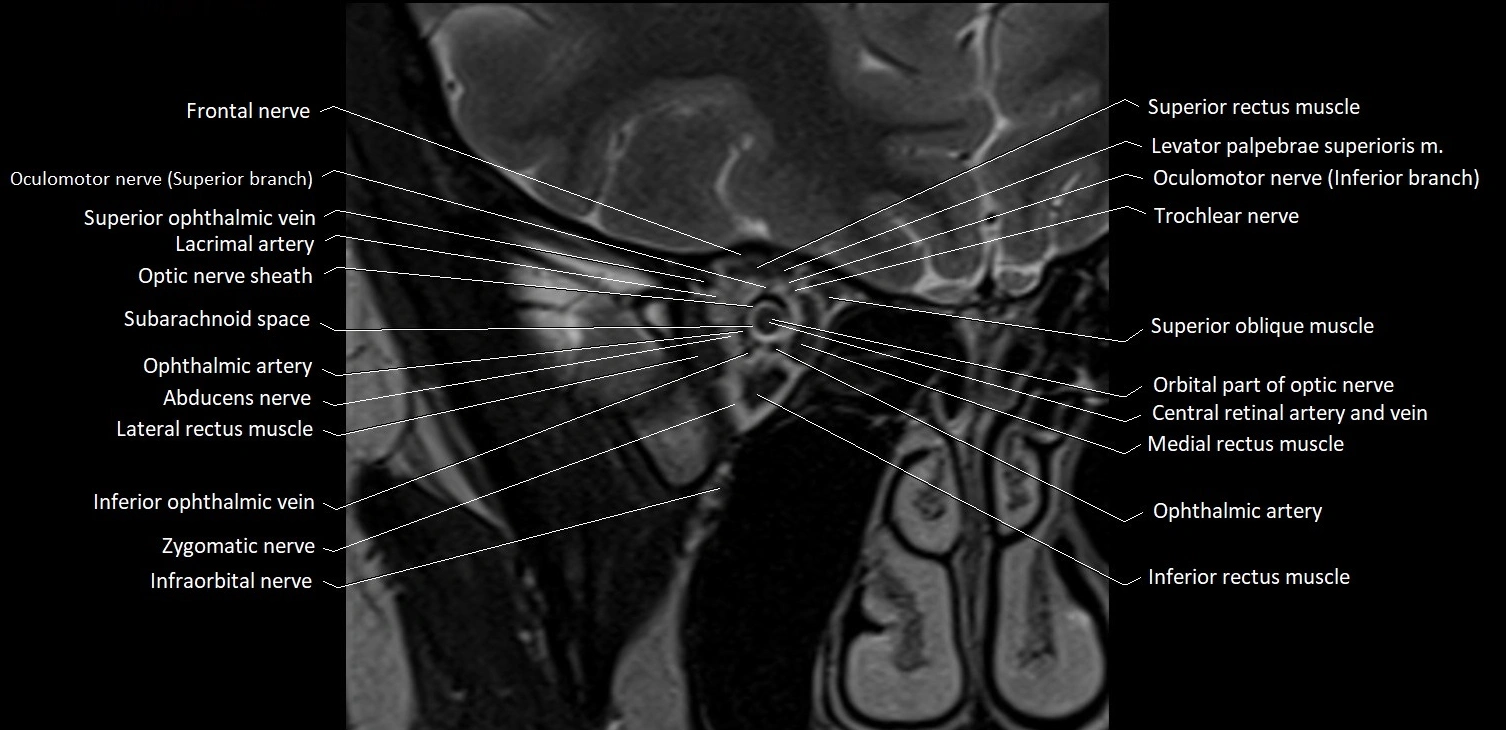

- Abducens nerve (Cranial nerve VI)

- Inferior ophthalmic vein

- Inferior rectus muscle

- Infraorbital nerve

- Lacrimal artery

- Lateral rectus muscle

- Medial rectus muscle

- Oculomotor nerve (Superior branch)

- Oculomotor nerve (inferior branch)

- Optic nerve sheath

- Orbital part of optic nerve

- Subarachnoid space of optic nerve

- Superior oblique muscle

- Superior ophthalmic vein

- Superior rectus muscle

- Trochlear nerve (Cranial nerve IV)

- Zygomatic nerve